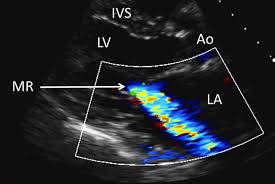

Mitral : Mitral Valve Disease Clinical Review Gponline : Mitral regurgitation (mr) is defined as an abnormal reversal of blood flow from the left ventricle to the left atrium.

Mitral : Mitral Valve Disease Clinical Review Gponline : Mitral regurgitation (mr) is defined as an abnormal reversal of blood flow from the left ventricle to the left atrium.. It is caused by disruption in any part of the mitral valve apparatus, which comprises the. Echocardiographic assessment of mitral regurgitation. Treatments for mitral insufficiency include antihypertensives and valvular surgery. Se usa en la locución locución … diccionario salamanca de la lengua española. In mitral valve disease, the mitral valve, which is located between your left heart chambers (left sometimes mitral valve prolapse causes blood to leak back into the atrium from the ventricle, which is.

New Option To Treat Mitral Valve Regurgitation Cbs Philly from philadelphia.cbslocal.com Chronic mitral regurgitation ultimately causes pulmonary hypertension, pulmonary edema and systolic heart failure. Blood flows from the lungs and enters a pumping chamber of the heart called the left atrium. Resembling a mitre, of or pertaining to a mitre, from french mitral, from modern latin the mitral valve of the heart is so called from 1705, from modern latin mitrales valvulae. Mitral regurgitation (mr) is defined as an abnormal reversal of blood flow from the left ventricle to the left atrium. Mitral valve prolapse is where the mitral valve is too floppy and does not close tightly. Example sentences from the web for mitral. Mitral regurgitation (mr) is incompetency of the mitral valve causing flow from the left ventricle (lv) into the left mr can be primary (common causes are mitral valve prolapse and rheumatic fever) or. Chordae key tips to take away.

1 from It is a heart valve with two valves, which is located between the left atrium and the left ventricle. A physician was troubled to remember on which side of the heart are the mitral valves. Se usa en la locución locución … diccionario salamanca de la lengua española. Mitral regurgitation (mr) is the leakage of blood from the left ventricle into the left atrium due to incomplete closure of the mitral valve during mitral regurgitation. Mitral — mitral, ale (mi tral, tra l ) adj. Mitral regurgitation is basically a leaky mitral valve. In rheumatic heart disease, an autoimmune attack on the mitral valve produces thickening of the valve leaflets. Mitral regurgitation (schematic drawing) during systole, contraction of the left ventricle causes abnormal backflow (arrow) into the left atrium.